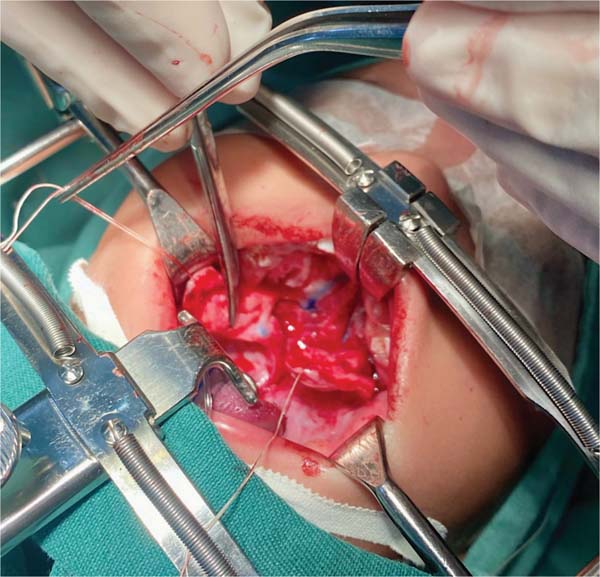

A nova tática cirúrgica foi projetada para reduzir a tensão na sutura na zona III de Pittsburgh, onde ocorrem 50% das fístulas. A zona III é uma área de transição entre os palatos duro e mole, com tecidos finos geralmente suturados em dois planos: um na mucosa nasal e outro na mucosa oral. O método proposto introduz um terceiro plano de sutura no periósteo, tecido mais resistente à tração, com um ou dois pontos em “U” utilizando Vicryl 4.0 (►Figs. 1–3).

A palatoplastia foi realizada sob anestesia geral, utilizando a técnica de dois retalhos mucoperiosteais com veloplastia intravelar, seguindo os princípios de Sommerland41 e com incisões relaxantes laterais. A sutura foi aplicada à mucosa nasal e à musculatura, com introdução do terceiro plano de sutura na zona de transição, utilizando um a dois pontos em “U” no plano do periósteo na porção distal do retalho mucoperiosteal. O fechamento da mucosa oral foi então realizado, e material hemostático foi colocado nas áreas cruentas. Os pacientes foram mantidos em dieta líquida por 7 dias, sem restrição de movimento das mãos e braços.